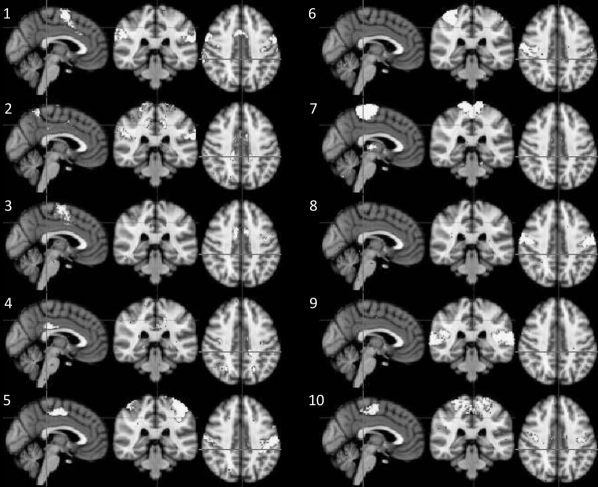

Figure 1: Illustrative resting-state fMRI dataset. We consider 10 spatial modes obtained using ICA, show in (a) and described in (b), each having a corresponding time series for each subject. All graphs that we present will adopt the vertex layout shown in (c). [A colour version of this figure is available in the online supplemental material.]

Exact algorithms are illustrated here with a small fMRI dataset consisting of six subjects from the Human Connectome Project (Van Essen et al.,, 2013). Scans were acquired on each subject while they were in a state of quiet repose; data from one 15 minute session were used, with a spatial resolution of 2Γ—2Γ—22222\times 2\times 2 mm and a temporal resolution of 0.7 secs; see Smith et al., (2013) for full details. After correcting for head motion, all data was registered to a common reference atlas space and 100-dimensional independent component analysis (ICA) was conducted on the temporally concatenated data. The result of this ICA was 100 spatial modes (common to all subjects) and 100 corresponding temporal modes (subject-specific); at this high dimension, the 100 spatial modes are sparse and spatially compact (though possibly bilaterally symmetric) and so essentially provide a data-driven parcellation of the brain. Hierarchical clustering was used on the ICA temporal modes following Beckmann and Smith, (2002), and the 10-mode cluster corresponding to motor cortex was selected for study here. Thus our data consists of 10 nodes, with a time series for each node for each subject. Figure 1(a) displays the neural regions that we consider and Figure 1(b) shows the approximate description of each region; note that region 4 was spatially diffuse and difficult to characterise, and thus is likely to be an artefactual component.